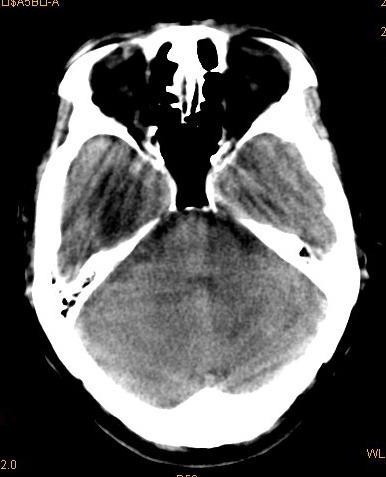

以下是引用卜一在2008-8-14 16:31:00的发言:[br]支持:巨脑回伴脑积水!另:胼胝体发育不良!

以下是引用随光逐影在2008-8-14 16:58:00的发言:[br]胼胝体发育不良;脑积水。

以下是引用同在2008-8-14 19:46:00的发言:[br]巨脑回伴积水,胼胝体发育不良.